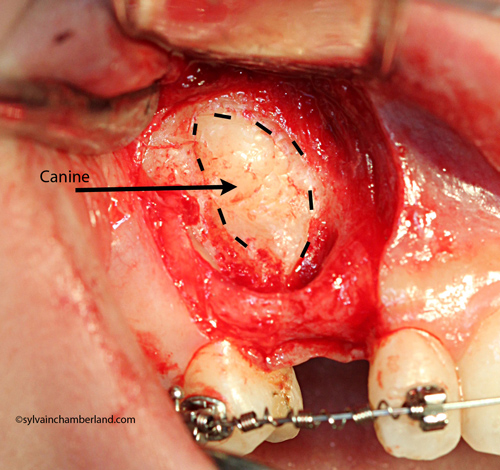

The picture on the left represents the ankylosed canine of case #2. The tooth crown is delimited by the dotted line. No space was visible between the enamel and the bone, confirming the ankylosis (fusion to the bone) of the tooth. The removal was the only possible option.